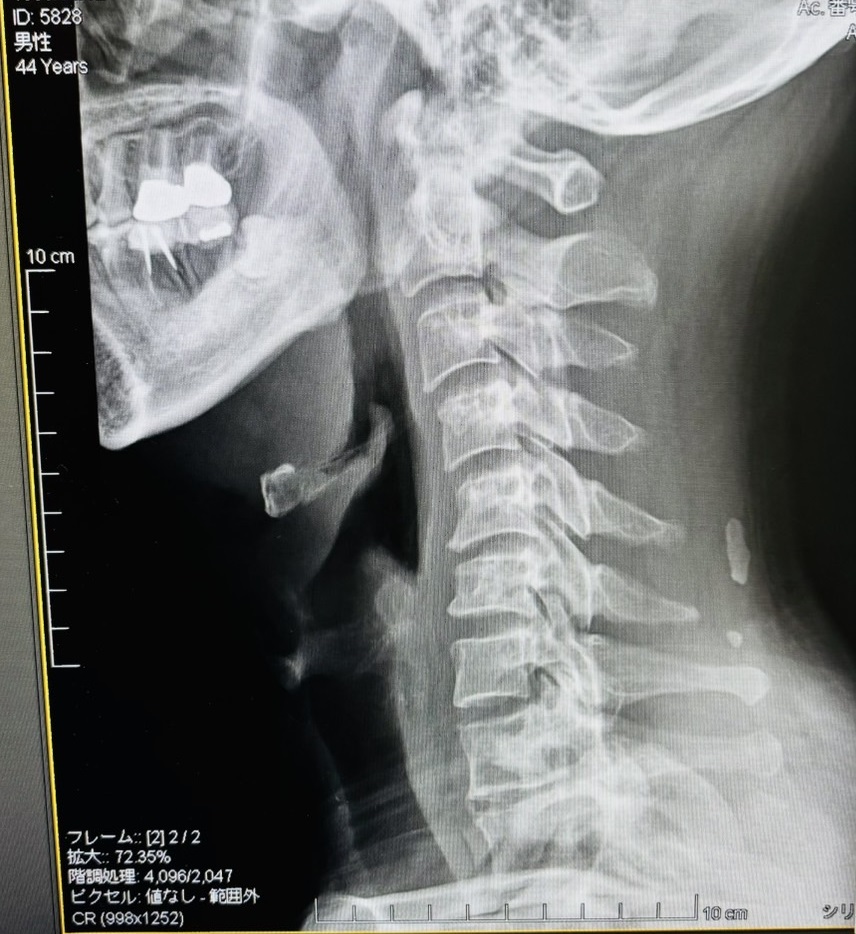

それにしても…「首、長いですね〜」と一言(笑)

そして、きれいなストレートネック!

先生に整体を紹介していただいたので、次回の診察で伺ってみようと思っています。